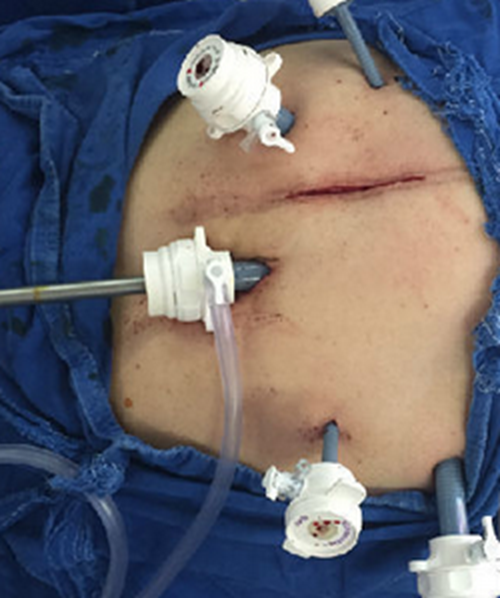

移植後腹水

移植鮮胚腹水